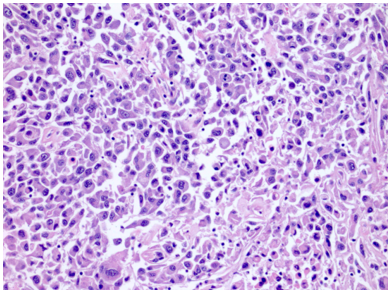

Vi thể

Mô tả vi thể (mô học) điển hình cho thấy khối u thường gồm các đám đặc tế bào, được chia cắt bởi các vách xơ–mạch máu không hoàn chỉnh,tạo nên kiểu phát triển bè rộng; kiểu sắp xếp dạng ổ hoặc dạng phế nang gặp íthơn. Các tế bào lớn với bào tương nhạt màu, dạng lưới mịn là đặc trưng nhất và xác định thực thể khối u này, trong đó thuật ngữ chromophobe phản ánh đặc điểm bào tương kém bắt màu. Xen kẽ là các tế bào nhỏ hơn với bào tương eosin. Các tế bào lớn có bào tương rất phong phú, đến mức trong một số mặt cắt, nhân không nằm trong mặt phẳng cắt nên tế bào có vẻ như không nhân, đây là một dấu hiệu gợi ý chẩn đoán mô học mềm. Ranh giới tế bào rõ, tạo hình ảnh giống tế bào thực vật.Có quầng sáng quanh nhân kiểu giả koilocyte. Nhân thường tăng sắc, màng nhân không đều và nhăn nheo, tạo hình ảnh dạng nho khô, kèm hiện tượng hai nhân khá thường gặp.

Hình 10. ChRCC thể điển hình được cấu tạo bởi các tế bào đa giác lớn với bào tương sáng, dạng lưới, xen kẽ với các tế bào nhỏ hơn có bào tương eosin. Lưu ý rằng các tế bào lớn có bào tương rất phong phú đến mức trong một số mặt cắt mô, nhân không nằm trong mặt phẳng cắt,khiến các tế bào này có hình ảnh như không nhân.